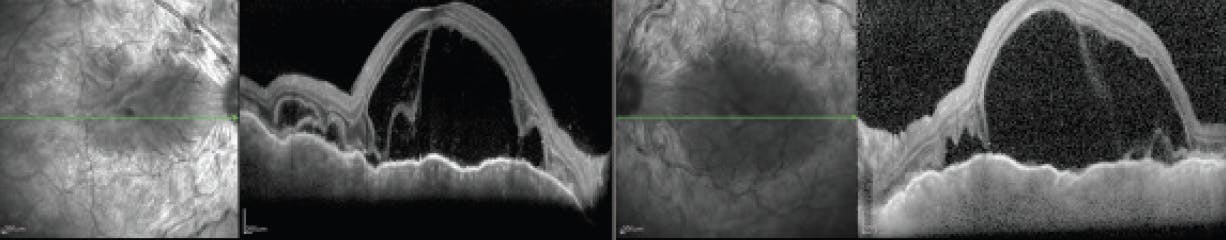

My patient enthusiastically assented to the 0.18 mg fluocinolone acetonide implant in each eye, reckoning the burden of microincisional cataract surgery to be small when weighed against the expected rewards: preservation of sight, durable uveitis suppression, and far fewer clinic visits and injections in the years to come. She is now approaching post-implantation year 2 and is seen just twice annually (Figure 3). The patient has required no rescue interventions to date, and her much-anticipated cataract surgery resulted in further visual gains.

<p>Figure 3. Nearly 2 years after the 0.18 mg fluocinolone acetonide implant procedure, the patient’s OCT demonstrates continued disease control.</p>

Figure 3. Nearly 2 years after the 0.18 mg fluocinolone acetonide implant procedure, the patient’s OCT demonstrates continued disease control.